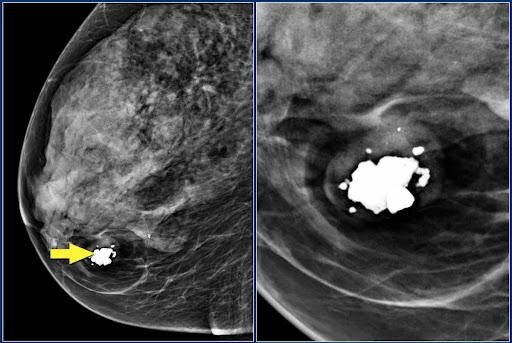

Что делать, если обнаружены кальцинаты

Такая «находка» на снимках требует дополнительных анализов. Необходимо определить тип образования: доброкачественный или злокачественный. Для этого проводят контрастную спектральную маммографию или рентген с контрастным веществом. Изменения на снимках оцениваются по форме, размеру, локализации, четкости и ровности границ, однородности структуры. Врач проводит классификацию по системе BI-RADS, когда образованиям присваивается категория от 0 до 6, где 0 — информации мало, нужны дополнительные обследования, 1 — норма, а 6 — злокачественное образование.